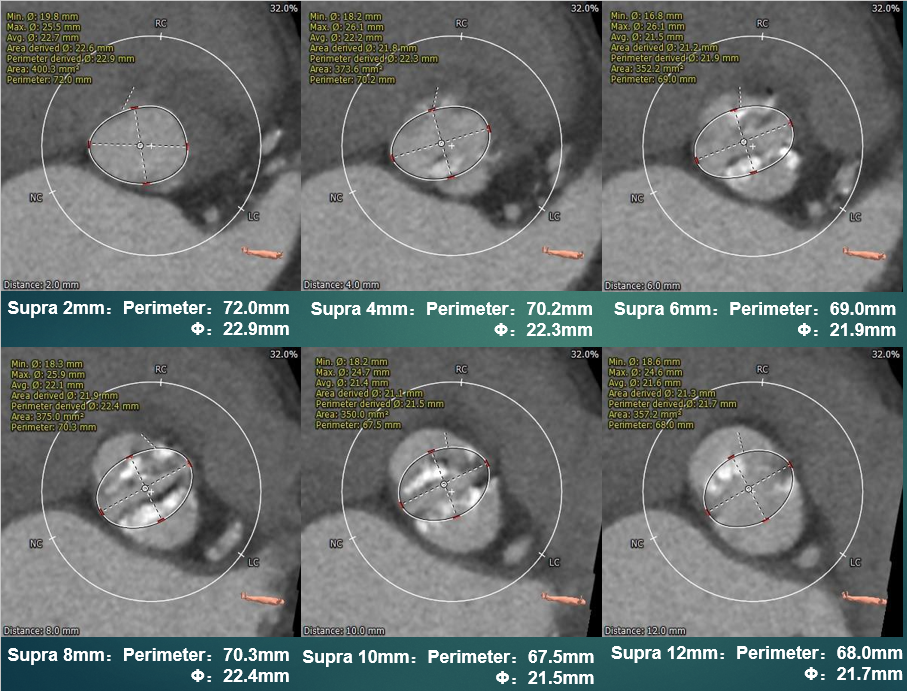

瓣上测量

瓣上测量:瓣叶中度钙化,钙化分布相对均匀,钙化主要分布在瓣叶边缘及瓣叶附着缘,锚定力量主要来源于瓣上6-10mm。